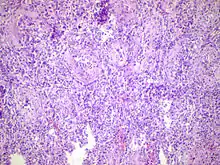

Acute epididymitis with abundant fibrinopurulent exudate in the tubules.